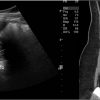

– Thận xoa trục, 2 cực dưới thận liên tục với nhau vắt ngang qua phía trước cột sống bởi nhu mô thận hay tổ chức xơ.

– Trên lát cắt dọc: không thấy rõ ranh giới cực dưới 2 thận.

– Trên lát cắt ngang qua đường giữa: 2 thận dính nhau, vắt ngang qua cột sống, phía trước động mạch chủ bụng.

– Có thể kèm theo các bất thường bất thường đường bài xuất, thận đôi, sỏi, nang thận hoặc u thận, sỏi gây giãn đường bài xuất.

=> Case lâm sàng 1: